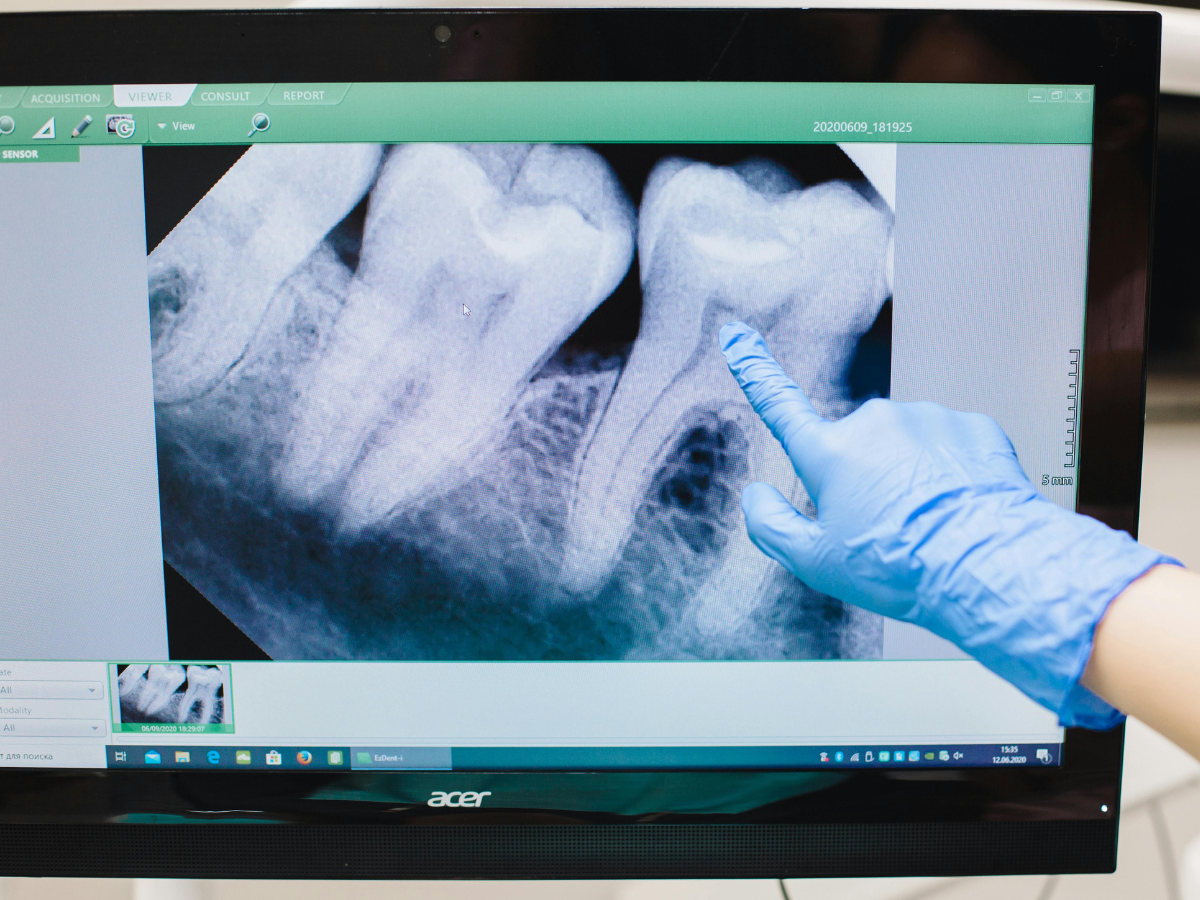

“Como no caso da influenciadora, uma mordida mais forte, um dente levemente quebrado ou dores na gengiva podem ser sinais de alerta”, explica. Por isso, ele recomenda visitas regulares ao dentista, além da realização de exames clínicos e de imagem para identificar fraturas, inflamações em estágios iniciais.

Caso algum problema seja detectado, o tratamento é individualizado. Uma fratura dentária, por exemplo, dependerá da gravidade do caso e das estruturas afetadas: “Em fraturas mais superficiais, que atingem apenas o esmalte ou a dentina, o dentista pode realizar uma restauração estética com resina composta, devolvendo a forma e a função do dente”, inicia.

“Quando há comprometimento da polpa dentária, com exposição dos nervos e vasos sanguíneos, é necessário um tratamento endodôntico, conhecido popularmente como tratamento de canal”, continua Cristiano Demartini. O procedimento consiste na remoção da polpa inflamada ou infectada, higienização do canal e o preenchimento com um material biocompatível para selar e proteger a região.

“Em casos mais complexos, como provavelmente ocorreu com a influenciadora, o dente pode ter sofrido uma trinca específica, em que a indicação seria a remoção do dente e a colocação de um implante para repor a estrutura perdida”, finaliza o dentista.